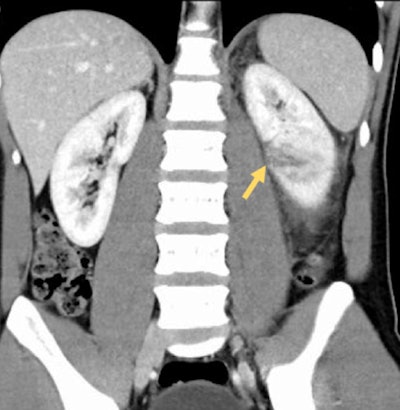

imaging (d) and (e), extravasation of contrast material from the collecting system of the lower pole can be seen. This patient subsequently underwent left nephrectomy.

In cases of penetrating trauma, preliminary noncontrast CT images may be of benefit in identifying and distinguishing extravasation from foreign bodies. If there is suspicion of an injury to the collecting system based on the initial scan, a delayed or excretory phase should be performed after 10 to 20 minutes. Injuries to the collecting system may be indicated on the initial scan by evidence of a laceration that appears to extend to the collecting system or by the presence of perinephric free fluid. Delayed-phase images also are useful in evaluating vascular injuries, such as active bleeding and pseudoaneurysm, the researchers noted.